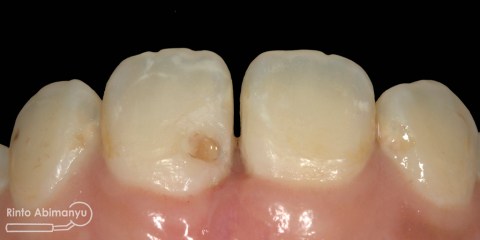

Kasus hari ini ceritanya datang seorang pasien wanita usia sekitar 50 an mengeluhkan gigi2 atas kirinya sering terselip makanan dan terkadang terasa senut-senut…

Pada pemeriksaan intra oral terlihat gigi 23 dan 24 mengalami karies dan cukup banyak sisa makanan terjebak disana…

Pemeriksaan respon dingin pun menunjukkan hasil negatif, untuk menambah data dalam penegakan diagnosis maka dilakukan pengambilan ronsen pada gigi2 tersebut

Terlihat dari ronsen tersebut karies pada gigi 23 24 sudah mencapai pulpa… dari informasi pemeriksaan klinis dan ronsen maka didiagnosis gigi tersebut nekrosis.. Saya jelaskan kepada pasien mengenai kondisi gigi2 nya dan rencana perawatan yang akan saya lakukan…